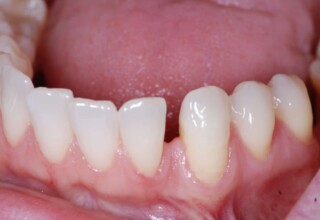

Full mouth prosthetic reconstruction on implants with a different approach on upper and lower jaw

Lower jaw: extractions, direct implant placement and immediate loading (same day) with a transitional bridge.

Upper jaw: Sequential extractions, sequential implant placement and gradual incorporation in the temporary bridge so that the patient was never left without fixed teeth. The aim of the above approach was to have the patient in continuous functional and aesthetic reconstruction, without immediate loading due to anatomical restrictions. Old smiling photos of the patient were used because the natural shape of the teeth was completely lost due to repetitive prosthetic attempts. Tooth relationship and teeth-lip support was transferred to the temporary restorations. Two different transitional bridges were needed to fully estimate phonetics, mastication and esthetics. After the necessary adjustments were finalized, the temporary bridge was used as a guide for the permanent bridges.